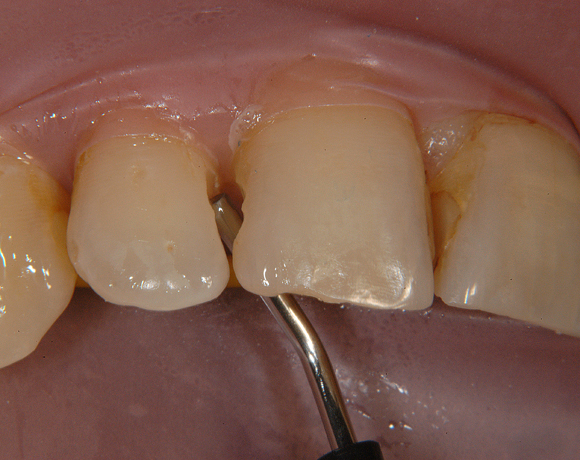

Bildlegende:

Bild 01 – 03: Ausgangssituation mit kariösen Läsionen und insuffizienten Füllungen